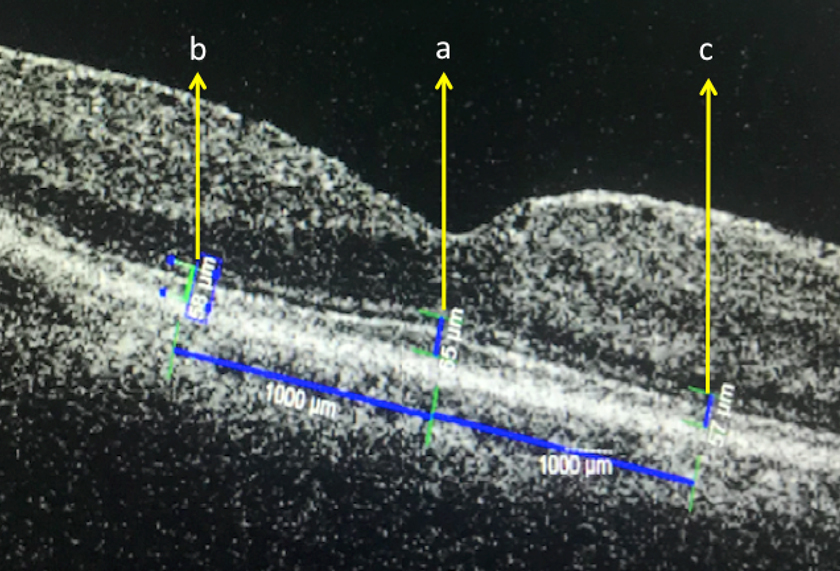

The entire macular area was scanned with an HDOCT instrument (Cirrus OCT; Carl Zeiss Meditec) with scan lengths of 9 mm for horizontal scans and 6 mm for vertical scans. High-quality images were obtained by using the five-line raster mode and en face analysis for IS-OS junctions. The distance between the inner border of the ELM and the ellipsoid zone (EZ),which had previously been called as the photoreceptor IS and OS junction line, was taken to be the IS thickness, and the distance between the EZ and the inner border of the retinal pigment epithelium (RPE) was taken to be the OS thickness. Photoreceptor thickness was taken from IS and OS thickness and measured in three locations : at foveola, 1000 µm nasal foveola (perifovea 1), and 1000 µm temporal foveola (perifovea 2). Central foveal thickness is distance from ILM to RPE thickness that was made on the OCT images passing through the fovea. This was made with the software of the system (Figure 1). Scans with a signal strength of >7/10 were considered appropriate, and a representative image was selected for the measurements.

Figure 1: Photoreceptor thickness in three locations: a. at foveola, b. 1000 μm nasal foveola (perifovea 1), and c. 1000 μm temporal foveola (perifovea 2).

Characteristics of patients are shown in Table 1. Mean age was 45.59±12.71 years with duration of detachment 36.07±28.99 days. Best corrected visual acuity (BCVA) preoperative had logMAR mean 1.59±0.64 (range : 0.7- 2.7) and post-operative with logMAR mean 1.00±0.61 (range : 0.3-2.4). Central foveal thickness was 114–418 µm with mean photoreceptor thickness at foveola was 43.85±10.81µm